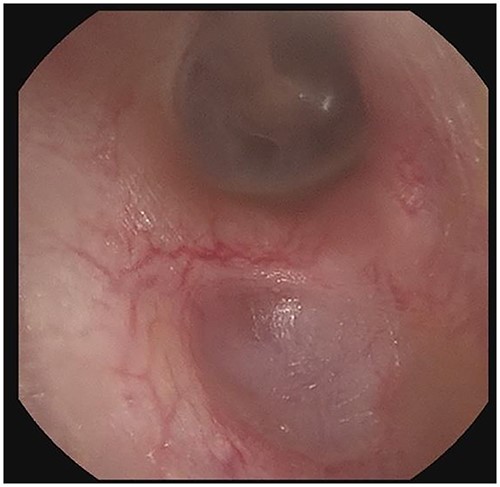

The patient evaluation and the data collection of this rare entity were performed in the senior author’s Otolaryngology practice in Poplar Bluff Regional Medical Center, Poplar Bluff, Missouri, USA (Table 1). Patient A, a 72-year-old female, was initially seen in 06/2015 and has been consistently followed for 87 months. On initial evaluation, the unusual clinical presentation triggered a workup with a CT of the temporal bone (Fig. 1), revealing a minor area of cortical erosion in the inferior wall of her right bony external auditory canal. Her initial presenting complaint was cerumen impaction on the right side associated with same side hearing loss. The patient has no history of diabetes, is treated with estradiol and progesterone tablets for hormonal replacement therapy and has no diagnosis of osteoporosis. Her blood pressure medications include atenonol and triamteren and has been on the same medications for the last seven years of our observation. The patient was managed with serial external auditory canal debridements, every 6 months. She had no history of otitis externa during the years of follow-up. Photographic documentation in her most recent visit (10/2022) revealed healthy appearing healthy mucosalization of the cavity and minimal amount of ceruminous debris (Fig. 2).

Right external auditory canal on patient A demonstrating excellent mucosalization of the indentation in the inferior aspect of the external auditory canal after serial cerumen debridement procedures in the office.